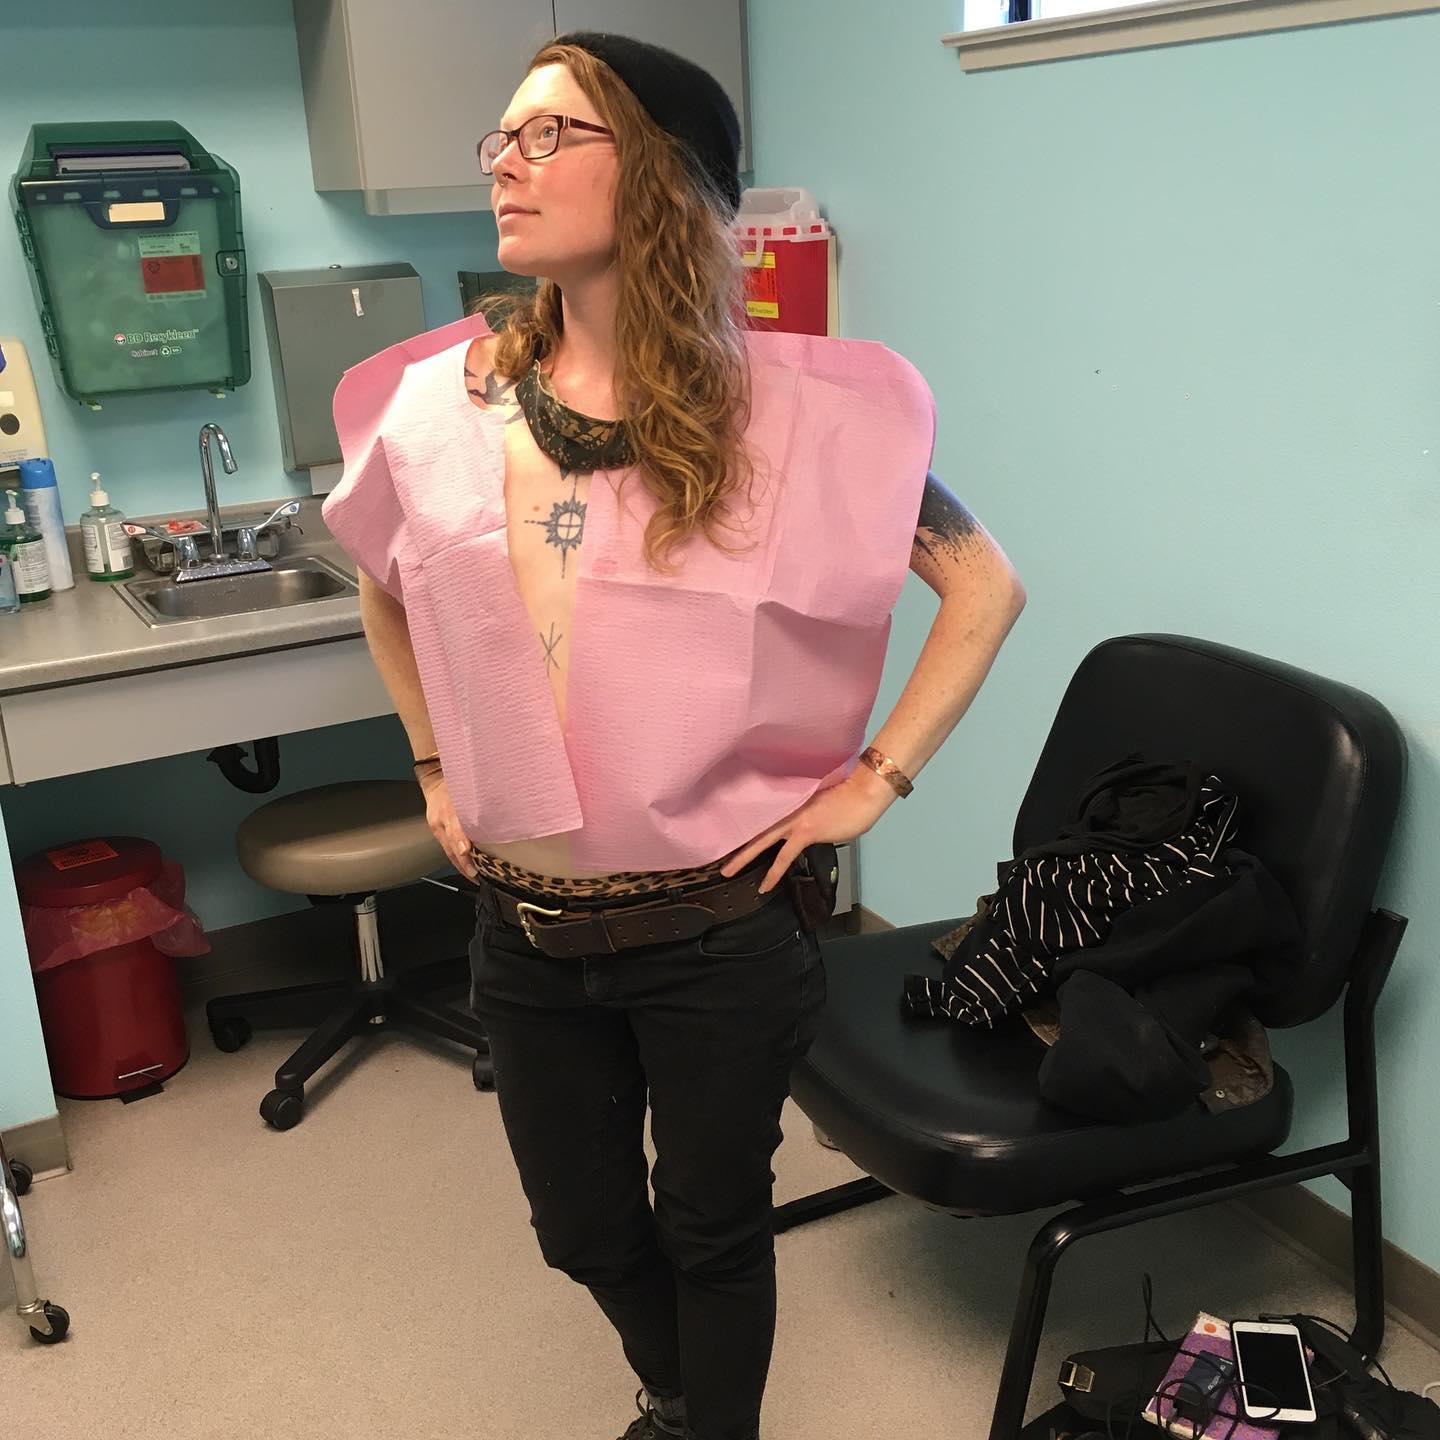

I’ve had this reflected a few times now, that when I am not writing and sharing what’s going on, people's hopeful default is that they assume I’m surrounded by love and support. I keep getting sweet messages that people are picturing me that way and I need everyone to know that my overall experience as of late has been that I’m terrified, alone, exhausted, and watching these tumors grow every single day, getting bigger and redder in my skin, pulling my nipple down. My nipple is folded over itself, moist and underneath it smells like rotting. I do have friends with me again, for the week, who are cooking, cleaning, loving me up, moved me into a new place, and supporting me enough that I finally have the time to share. I started writing over a week ago, (rather, I spoke this into a recording and my friend Z transcribed) but already so so much has changed and it’s so much work to edit it all over again. I’ll do my best, and my hope is that with this long update I can get back on track and share more easily in shorter more frequent doses. That is, if I continue to have support again, which I have felt to be far too lacking over the last few weeks.

I’ve been going through a really intense experience. I have been barely sleeping for weeks and weeks and am in increasing amounts of pain as the tumors in my chest are growing. I haven’t shared an achingly painful piece publicly until now: On the anniversary of my mom's death, October 11th, I found out that I was pregnant, which is something that I've wanted so, so badly. A few days later, Jimmy left for up north. A week and a half later, I found out through a FNA (fine needle biopsy) that the lumps in and around my nipple are cancer recurrence as well as metastasis to further lymph nodes- one confirmed in my collar bone.

As much as I wanted to share this news, I was so disheartened at different times when I would tell various friends or practitioners and get responses such as: “CONGRATULATIONS!! HOORAY!” No. That was not the feeling, and not what you say to someone in the throes of a life-threatening illness when they tell you they are pregnant. I felt a deep heartbreak, longing, and despair for the reality of my life situation: that as much as I yearned it to be so, I could not continue with this pregnancy. I had to start curating how I told the few people I could. I felt afraid to share because of the variety of judgements for my choice if I either continued to maintain or terminate the pregnancy. I became fearful for the support I might lose if I chose either path. The symptoms of the pregnancy were getting so intense, I could not continue with any more of my treatments, I could not eat the specific foods that i was trying to eat, could barely eat anything for a while. I had to ditch everything and just eat biscuits and gravy and pasta and whatever I could keep down. I cannot describe the feelings I experienced while watching my body change and grow and swell with pregnancy, while also watching the tumors grow redder, and my nipple get crustier and more unhealthy every day. Walking between the worlds of life and death.

i have felt totally miserable. it’s a chore dragging myself around. i’ve been afraid of how much i just want to sleep. is it okay? is it too much? am i supposed to push myself to move and walk? people remind me that going through radiation (which i just finished friday) leads to cumulative fatigue and peaks the 3 weeks following radiation. i just had no idea it could be like this. and i think there’s still fine-tuning with meds to be done. the long acting morphine i was prescribed feels like too high a dose. but there’s no long-acter at a lower dose available so they tell me.

i had another procedure this afternoon, drained another 850ml of fluid from around my lungs. this time went way better than the last; they went slower and didn’t puncture my lung like last time at the marin hospital. i felt calm and supported and feel some relief.